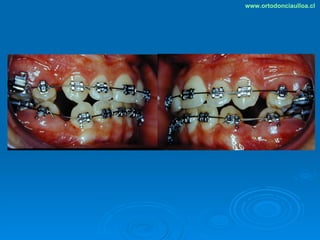

Este documento presenta dos casos clínicos de pacientes que recibieron tratamiento de ortodoncia. El primer caso fue de una paciente femenina de 14 años con apiñamiento dental y mordida cruzada que fue tratada mediante extracción de premolares y alineamiento dental. El segundo caso fue de un paciente masculino de 14 años con clase II esqueletal y desarmonía dentomaxilar que fue tratado con extracción de premolares y corrección de mordida. Ambos casos mostraron mejoría después de 3 años de tratamiento.